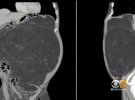

63-річному Кевіну Дейлі з американського міста Хобокен, штат Нью-Джерсі, вирізали 13 кг пухлину. Вона була розміром з пляжний м'яч і росла в організмі близько10 років.

Живіт виглядав, як у чоловіків, які часто п'ють алкогольПроте Кевін не вживав алкоголю. Щоб дізнатися в чому причина, він записався на сканування. Воно показало, що це ліпосаркома - рак черевної порожнини, який починається в жирових клітинах.

"Хоча ці пухлини великі і злоякісні, вони повільно ростуть і схильні не давати метастази", - сказав Хуліо Тейшейрі, хірург з лікарні Ленокс Хілл із Нью-Йорка.

Лікарі витратили на операцію 6 годин, щоб витягти це новоутворення одним шматком і не пошкодити органи черевної порожнини. Також довелося видалити одну з його нирок, тому що пухлина обернулася навколо неї.

Після цього Кевіну не потрібна хіміотерапія або опромінення, тому що це повільно зростаюча пухлина з невеликою схильністю до метастазування, але про всяк випадок він буде контролюватися МРТ.